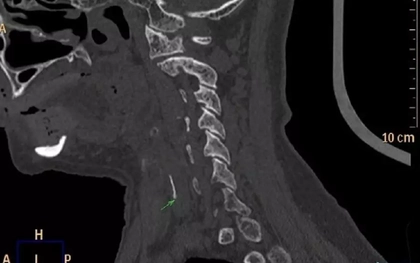

Nuốt cơm thật nhiều, khạc nhổ liên tục, ngậm vitamin C sủi hay uống nước chanh, giấm… là những “mẹo” truyền miệng được không ít người áp dụng khi bị hóc xương cá. Bác sĩ cảnh báo, đây là những cách xử trí phản khoa học, chẳng những không lấy được dị vật mà còn đẩy người bệnh vào tình huống nguy hiểm đến tính mạng.